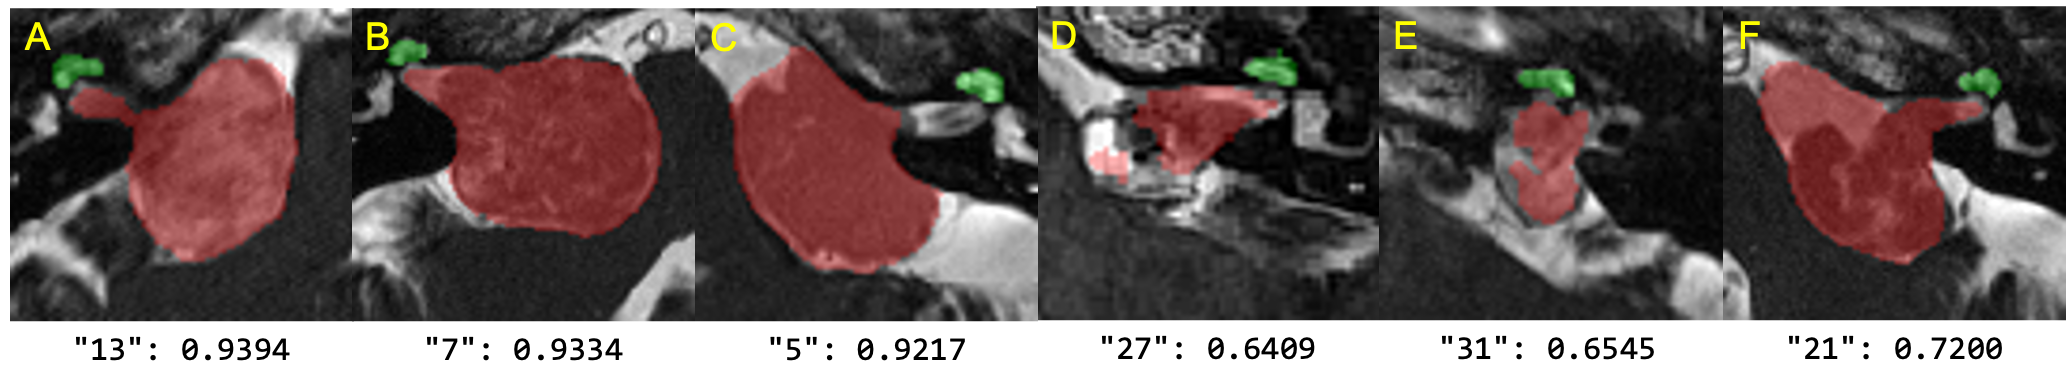

Refer to caption

Figure 3: Qualitative results on the validation set. A to C and D to F display the best and worst VS segmentation results. The image ID and the corresponding dice score are also shown. Our experiments show that VS tumors with higher inhomogeneity, e.g., D, are more difficult to segment.